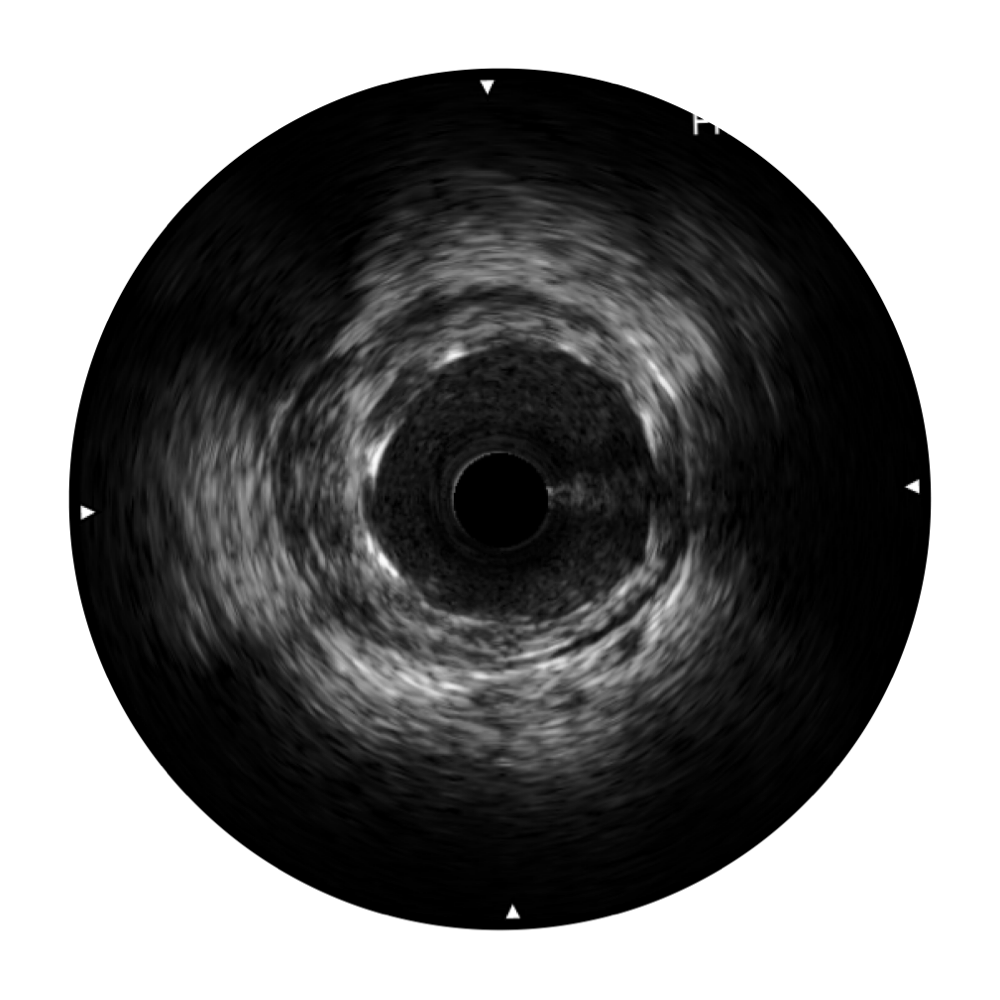

血管内超声(IVUS) 通过对病变程度、性质和累及范围的精确判断,可帮助选择治疗策略和方法,指导介入治疗过程,能够降低主要不良心血管事件,改善预后,在复杂病变介入治疗中用于指导支架置入的优势更为明显。血管内超声(IVUS)已成为精准心血管介入治疗的“金标准”。

1xBET超宽频成像技术覆盖20-80MHz1或20-90MHz2频率范围, 提供优异的分辨力同时也保证充足的穿透深度

对比传统IVUS导管成像,1xBET宽频IVUS图像的近场支架梁显影更细腻,远场中膜外血管仍清晰可辨,兼顾远中近,兼顾分辨力与穿透深度